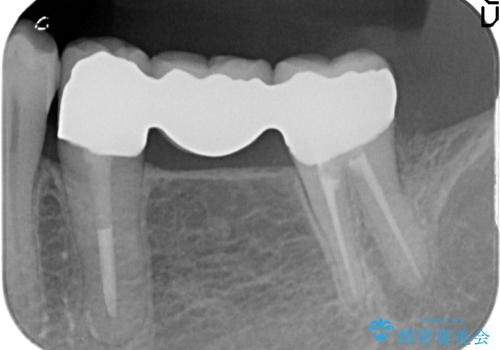

- 他院にて左下奥歯のポケットが深いと言われた、銀歯と歯茎の隙間も気になるのでまとめて治療して欲しいと来院された方の症例です。

左下7の遠心部は部分的な骨欠損によるポケットが10mmあったため、再生療法による骨の再生を行いました。

骨の定着を待ちポケットが3mm(正常範囲内)であることを確認後、オールセラミッククラウンによる欠損補綴を行いました。

今回用いたオールセラミッククラウンはジルコニアフレームという白い素材の上にセラミックを盛っているため、審美性が非常に高いのが特徴です。

また、ジルコニアは人工ダイヤモンドの材料にも使われているほど高い強度を持っており、そのためオールセラミッククラウンは審美性だけでなく、奥歯やブリッジの補綴も可能とするクラウンです。